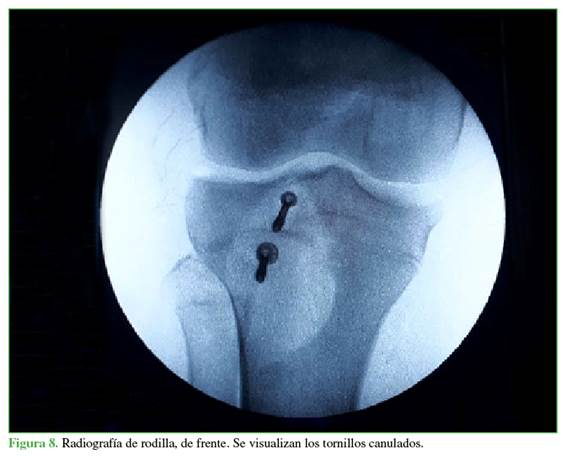

La cirugía consistió en una reducción abierta más osteosíntesis con colocación de dos tornillos paralelos sin afectar la fisis (uno en la región de la metáfisis y otro en la región de la epífisis). Durante la operación, se constató la lesión del tendón rotuliano con invaginación de las fibras distales en el foco fracturario, se continuó con su liberación y se realizó una sutura a nivel del periostio, en la región anterior de la tibia proximal (Figuras 4 y 5), se procedió a la reducción y osteosíntesis con dos tornillos paralelos de 3,5 mm y la colocación de arandela, ubicados en la epífisis y la metáfisis (Figuras 6-8). Se le colocó un yeso cruropedio en extensión sin carga por seis semanas para luego continuar con el tratamiento de rehabilitación (Figura 9).

El tipo de material que utilizamos al igual que otros autores (Balmat y cols.)10 son dos tornillos canulados con rosca incompleta más arandela, colocados en paralelo, uno en la epífisis y otro en la metáfisis salteando la fisis, explorando previamente el trazo fracturario por presentar interposición del tendón rotuliano sin la colocación de cerclaje, a diferencia de Nikiforidis y cols. que utilizan ese método de cerclaje, rehabilitación precoz sin inmovilización y marcha sin carga asistida con muletas hasta la sexta semana para continuar con el retiro del cerclaje en la octava semana, y necesitan un segundo tiempo quirúrgico para el retiro del material, lo que demora el retorno al deporte y provoca casos con atrofia de cuádriceps. También tenemos diferencias con Pesl y Havranek, quienes realizan una primera fijación interna con colocación de tornillos percutáneos como primer intento obviando la exploración tendinosa; en este caso, el tiempo de inmovilización, la carga completa y el retorno a la actividad deportiva fueron más rápidos, iguales a los descritos por Agrelo y cols., y Casas-López y cols. En nuestro caso, no fue posible realizar una resonancia magnética como sugieren Tuca y Pineda11 por no disponer de un resonador y porque el paciente no tuvo síntomas meniscales en los controles clínicos.